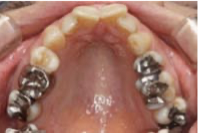

「主訴が不正咬合であっても口呼吸が疑われる場合には、患者さんの健康を第一に考えて、まず口呼吸を改普することが先決です。検査の際に、低位舌は視診で、大きなアデノイドや狭い気道はセファロで確認することができます。中学生・高校生になってから不正咬合を治療するよりも、小児期に治療する方が早期に大きい効果が得られます。」(保田)。具体的な治療方法は、矯正装置(写真下)を用いて上顎を拡大することによって鼻腔の拡張を促し(写真上)、呼吸時の鼻腔の抵抗を減らし、口呼吸を・鼻呼吸に改善し、適正な舌位を獲得するという流れになる。